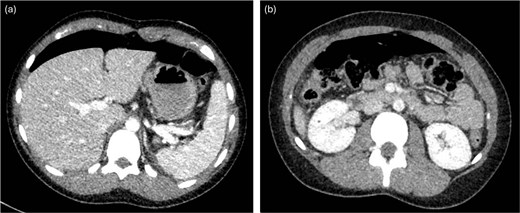

Laparoscopy began with placement of a 5 mm umbilical trocar and two additional 5 mm trocars in the right and left abdomen. Turbid fluid was encountered and suctioned. In the upper-abdomen, significant inflammatory omental adhesions were found against the right upper quadrant and gallbladder. A complex fluid collection with inflammation was identified in the left upper quadrant (Fig. 2). These inflammatory adhesions were carefully dissected using a Cool-SealTM device to visualize the pylorus and duodenum; however, inflammation around the gallbladder prevented full release of these adhesions. Mobilization of the gastrocolic ligament revealed a normal posterior gastric wall. Because inflammatory exudates obscured the anterior stomach and the first and second part of the duodenum, making the perforation’s origin (duodenal or gastric) initially unclear, simultaneous intraoperative-endoscopy was requested for precise localization.

Intraoperative pictures demonstrating the sequelae of the hollow viscus perforation. The pictures in (a) and (b) demonstrate contamination and associated inflammatory adhesions in the left and right upper quadrant, respectively. The pictures in (c) and (d) demonstrate the antral perforation. The tip of the Maryland dissector was able to insert into the perforation (d) to assist with identification of the perforation endoscopically for closure.

The gastroenterology team performed concurrent endoscopy using. With air insufflation and transillumination, a small pinpoint perforation was clearly identified on the anterior surface of the gastric-antrum (Figs 2 and 3).

To aid endoscopic visualization of the small perforation, a Maryland grasper was gently inserted into it (Fig. 2); the grasper’s tip, visualized endoscopically, confirmed the exact location. The remainder of the esophagus, stomach, and duodenum appeared normal. The Overstitch™ endoscopic-suturing device, mounted on a double-channel therapeutic endoscope and utilizing a tissue-helix for full-thickness bites, was used. Three full-thickness inverted figure-of-eight 2–0 Prolene sutures were placed at the perforation. Laparoscopic visualization confirmed full-thickness suture placement before the sutures were cinched, effectively closing the gastric wall defect (Fig. 3).